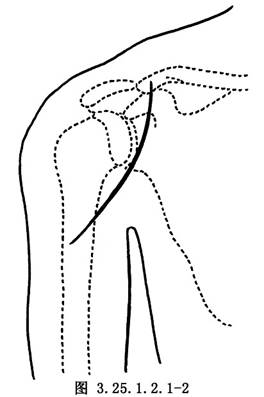

三角肌前內側縱行切口,切開皮膚及皮下組織(圖3.25.1.2.1-2)。